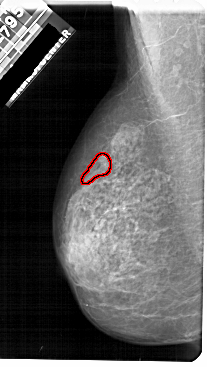

A_1722_1.LEFT_CC

LEFT_CC LINES 5071 PIXELS_PER_LINE 2626 BITS_PER_PIXEL 12 RESOLUTION 43.5 OVERLAY

FILE: A_1722_1.LEFT_CC.OVERLAY

TOTAL_ABNORMALITIES 1

ABNORMALITY 1

LESION_TYPE CALCIFICATION TYPE PLEOMORPHIC DISTRIBUTION SEGMENTAL

ASSESSMENT 4

SUBTLETY 2

PATHOLOGY MALIGNANT

TOTAL_OUTLINES 1

BOUNDARY